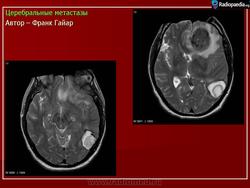

ГМ. Церебральные метастазы. +

Церебральные метастазы.